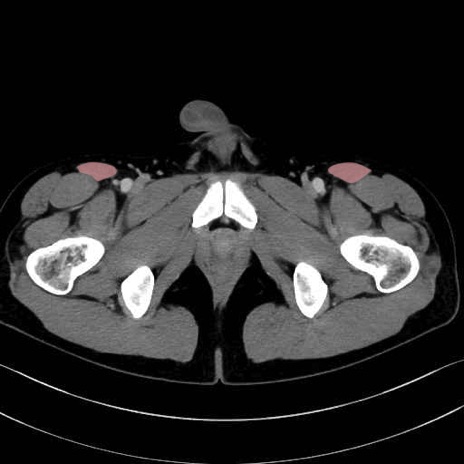

縫工筋 (Sartorius)